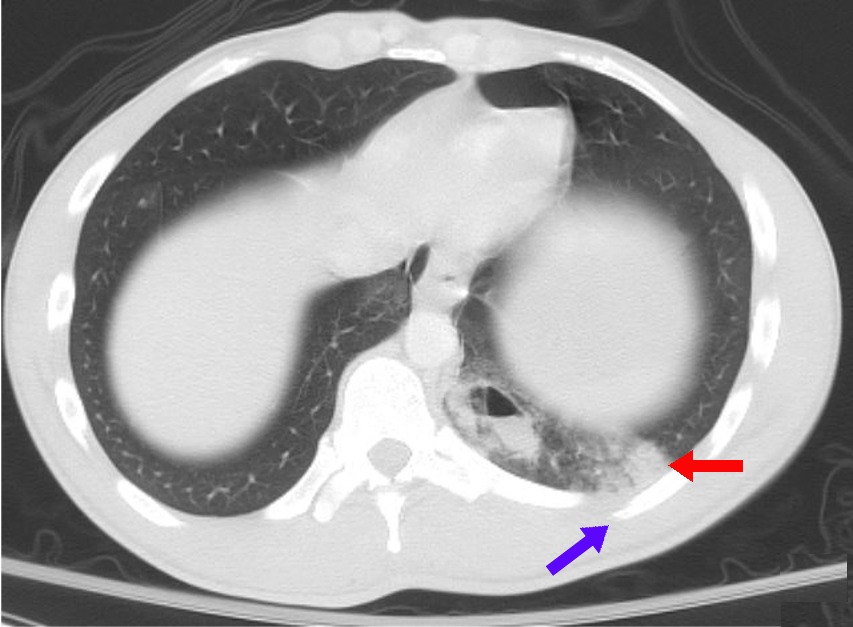

CT — Pulmonary Contusion (Annotated)

Axial CT showing pulmonary contusion with ground-glass opacification and consolidation following chest trauma

CT Downloaded 2026-03-15

Ct

Lung Window 120 kVp W:1500 L:-600

Wikimedia Commons: Pulmonary contusion CT arrow.jpg

CT — Pulmonary Contusion

CT showing bilateral pulmonary contusions with patchy areas of consolidation

Wikimedia Commons: Pulmonary contusion CT.jpg